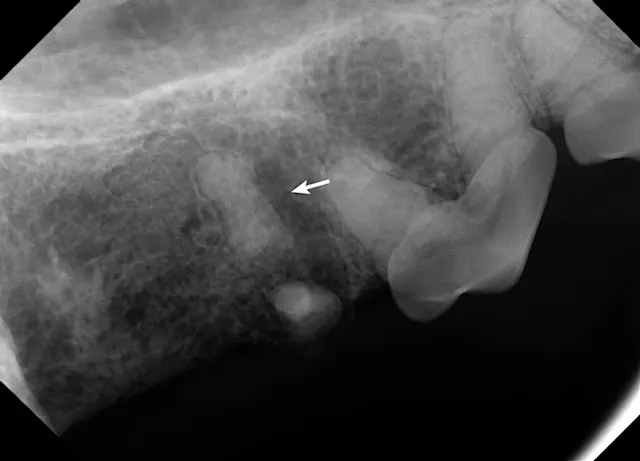

Dental radiographs confirmed the root fragment of the right maxillary fourth premolar had been retained (Figure 4). Periapical rarefaction (ie, periapical lucency) and periodontal disease of the right maxillary canine were also confirmed on radiographs; comparison with the contralateral left maxillary canine revealed that the canine tooth had been nonvital for several months, as the pulp cavity of the right maxillary canine had failed to narrow (Figures 5 and 6).1 Dental radiographs of the left maxillary fourth premolar revealed fractures of the mesiobuccal and mesiopalatinal roots in addition to advanced periodontal disease of the distal root (Figure 7).